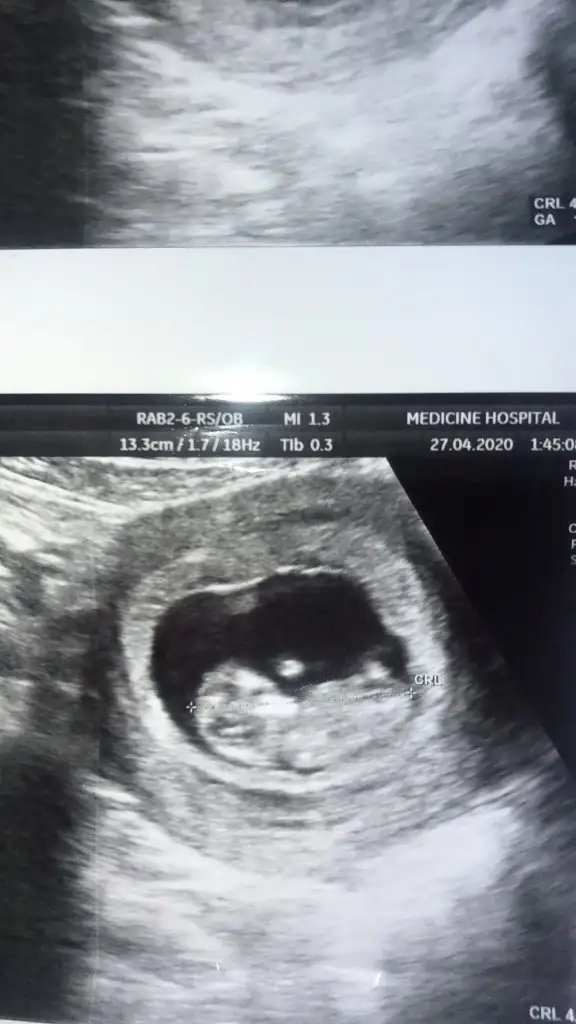

Merhaba bizim de 13. Hafta böyle sizce nedir :)Slm arkadaşlar nub teorisi konumuzda yaptıgım tahminleri ankete tıklayın yuzdesini görelim

11 yada 12 yada 13 hafta Nub usg nizi konumuza paylaşın

Diger konumda kız sanki eminde değilim yazdımMerhaba bizim de 13. Hafta böyle sizce nedir :)